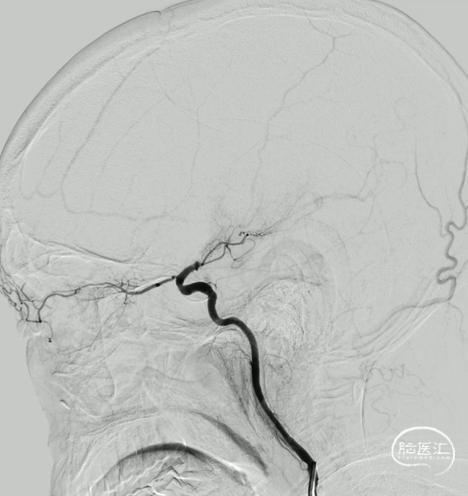

右侧大脑中动脉起始部闭塞,左侧前交通开放,左侧大脑前动脉通过软膜支代偿,大脑后动脉通过软膜支代偿,侧支代偿可,考虑粥样硬化合并急性闭塞的可能。

微导丝、微导管通过闭塞段,微导管造影真腔。

回退微导管,做微导管首过效应。

微导管首过效应:阴性。

路图指引下,将微导管重新超选至下干。

微导丝、微导管辅助,跟进中间导管至颈内末端。

球扩后造影:狭窄明显改善,前向血流明显好转,未见血栓征象,球囊部分回收支架,撤出。

观察15min,未见弹性回缩,正侧位造影。